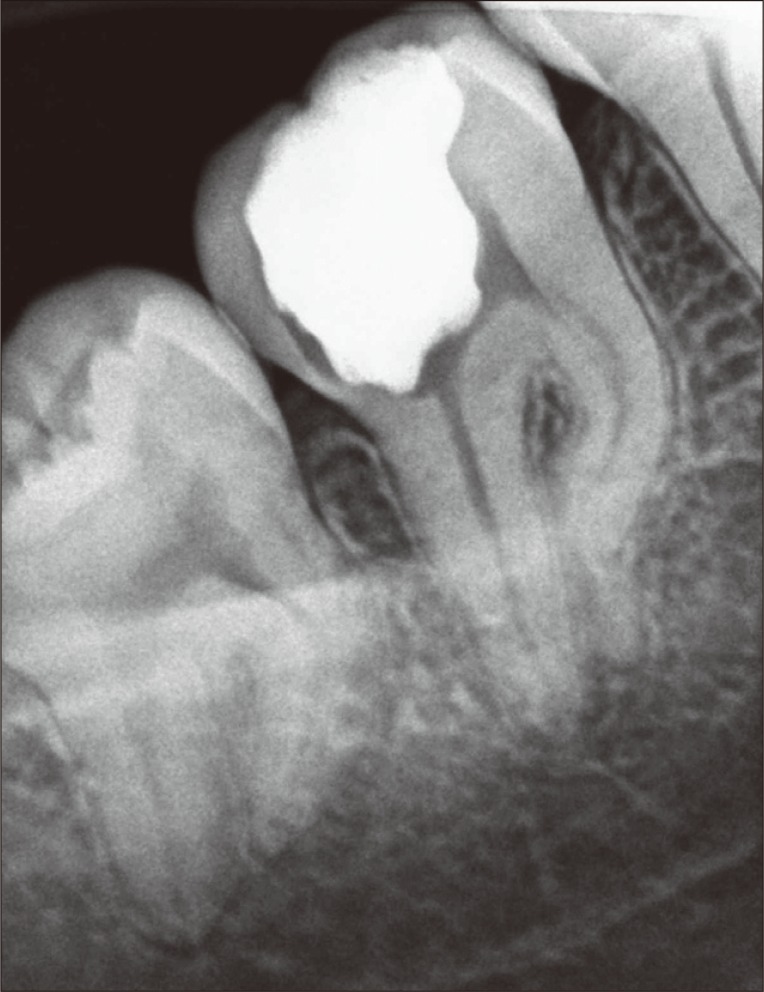

Next, the pulp chamber was cleaned to remove the excess of gutta-percha and sealer. Glass-ionomer restorative cement (Vidrion R, SS White, Rio de Janeiro, RJ, Brazil) was used as temporary restoration due to its good sealing ability and fluoride release. After 2 weeks, the tooth was definitely restored with composite resin (Z250, 3M ESPE, Sumaré, SP, Brazil) (Figure 2). Continued follow-up over 6 months has shown a successful outcome from endodontic perspective (Figure 3). Clinically, the tooth presented no painful symptomatology, and radiographically, no signs of failure in root canal filling or periapical lesions were observed.